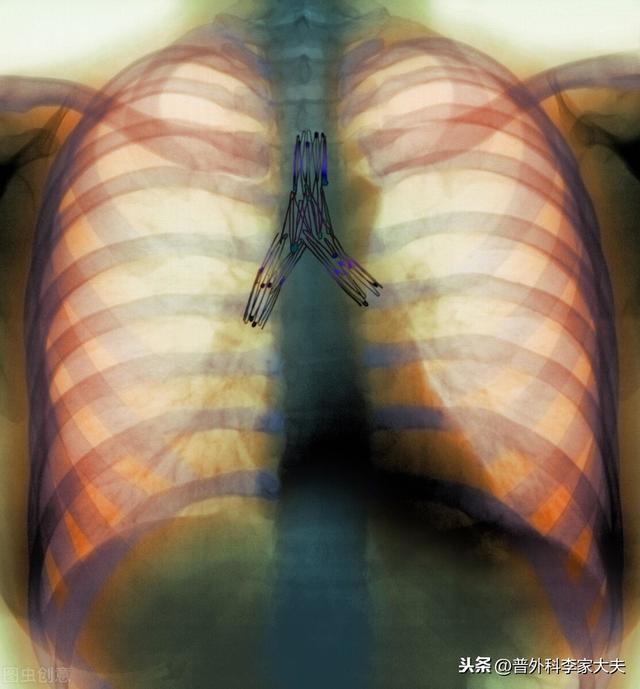

胸腔鏡下肺手術

0期や1期の早期非小細胞肺がんの患者さんが、肺がんの真の根治切除である手術を受けた場合、術後補助化学療法やその他の標的療法は必要ありません。手術後に患者さんがしなければならないことは、肺がんの再発を防ぐことです。上記のように肺がんの発がん因子を取り除き、肺がんの定期的な経過観察・見直しがしっかり行われていれば、一般的には、この種の患者さんは術後半年に1回、2年以降は1年に1回、全身の検査を受けた方が安心です。

ステージ2、3の非小細胞肺がん患者の場合、肺がんの根治切除は行われている。しかし、理論的にも事実としても、本当の意味で肺癌が治癒したわけではなく、体内に残存する肺癌細胞が再発する危険性があることも明らかである。 そのため、現在の国内外の肺癌診断・治療ガイドラインから、これらの肺癌手術患者には、術後補助化学療法や分子標的治療などの総合的な治療を行うことが求められている。もちろん、術後化学療法をどのように行うか?比較的単純な言い方をすれば、肺癌診断・治療ガイドラインの原則に忠実に従うことを基本に、患者の実情に応じて微調整を行い、ガイドラインで紹介されている治療計画をより患者の状態に適したものにすることができる。また、上記のように肺がんの発がん因子を除去し、肺がんの定期的な経過観察・検診をしっかり行うことも必要であるが、前述のように肺がんの手術を受けた患者は体内に肺がん細胞が残存しているリスクが懸念されるため、それに対応する定期検診の間隔は短くせざるを得ず、一般的には1年目は3ヶ月に1回、2年目は6ヶ月に1回、2年目以降は1年に1回となる。主な検査項目は、胸部CT、腹部超音波またはCT、全身骨スキャン、いくつかの定期的な血液検査である。